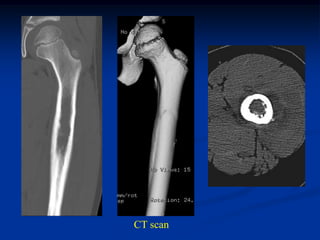

Case #222                       CT scan

65 year female with chordoma sacrum and buttock

tumor

Axial T-2 MRI

Axial T-2 MRI at higher level

femur

Sagittal T-2 MRI

CT scan